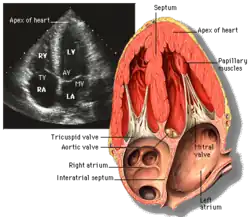

Echocardiography

Echocardiography is regularly utilized to diagnose, manage, and monitor patients with suspected or established heart ailments, making it a highly prevalent diagnostic imaging technique in cardiology due to its speed and efficiency.[3]

Transthoracic echocardiography (TTE)

Transthoracic echocardiography (TTE) uses ultrasonic waves for continuous heart chamber and blood movement visualization. It is the most commonly used imaging tool for diagnosing heart problems, as it allows non-invasive visualization of the heart and the blood flow through the heart, using a technique known as Doppler.